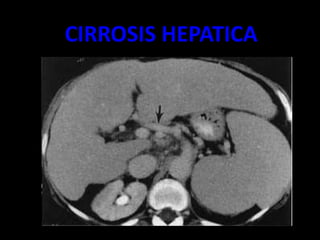

CIRROSIS HEPATICA

• Volumen hepático disminuido, bordes ondulados

• Parénquima con hiperecogenico, formado por ecos gruesos y

con atenuación posterior.

• VP incremento de diámetro, por encima de 14mm.

• VSH disminuidas de diámetro.

• VCI sin latido trasmitido

• Hipertrofia del segmento I, con hipoecogenisidad

• Ascitis

• Esplenomegalia

Ascitis

Bordes ondularos

irregulares

Lobulo hepatico

derecho diminuido

de tamaño

CIRROSIS HEPATICA:ASCITIS

– EXISTE UNA DESTRUCCION MASIVA DE LOS

HEPATOCITOS , POR TANTO HAY UNA PERDIDA

DE LA ARQUITECTURA DE LA FORMA HEPATICA.

– TIPOS LAENNEC

– POSNECRÒTICA

– BILIAR ( SECUNDARIA A LA COLECISTITIS

INTRAHEPATICA CRONICA)

– INFILTRACION GRASA

– HEPATOMEGALIA

– FIBROSIS

– HIPERTENSIÒN PÒRTAL

– CONTORNOS LOBULADOS E IRREGULARES .

– ATROFIA DEL LOBULO DERECHO E HIPERTROFIA

DEL IZQUIERDO.(AL)

– ASCITIS.